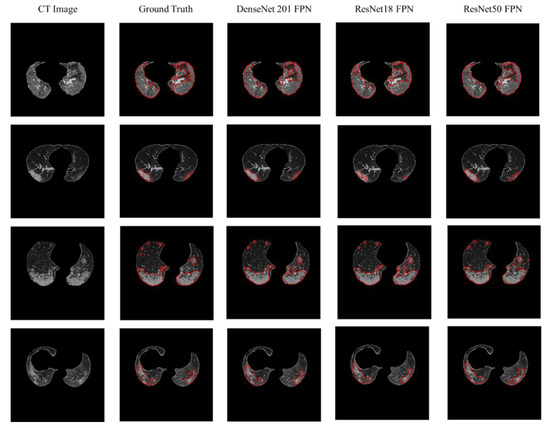

4.2. Lesion Segmentation